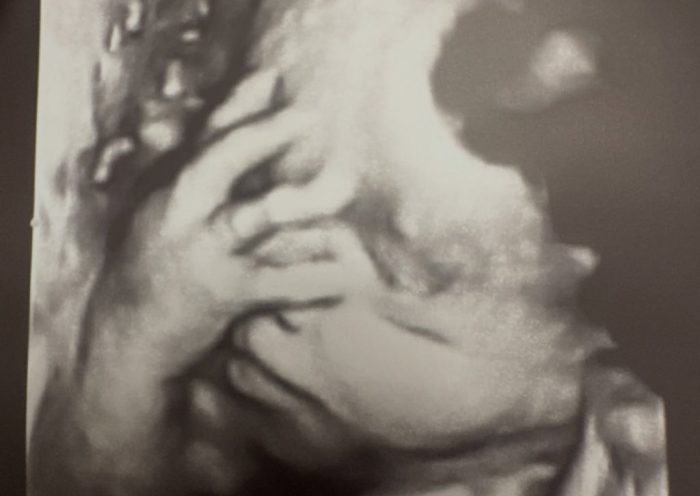

Troian Bellisario și Patrick J. Adams, părinți pentru a treia oară! Actrița din Pretty Little Liars a născut al treilea copil

Troian Bellisario și Patrick J. Adams au anunțat că au devenit părinți pentru a treia oară. Actrița din „Pretty Little Liars” și actorul din „Suits”…